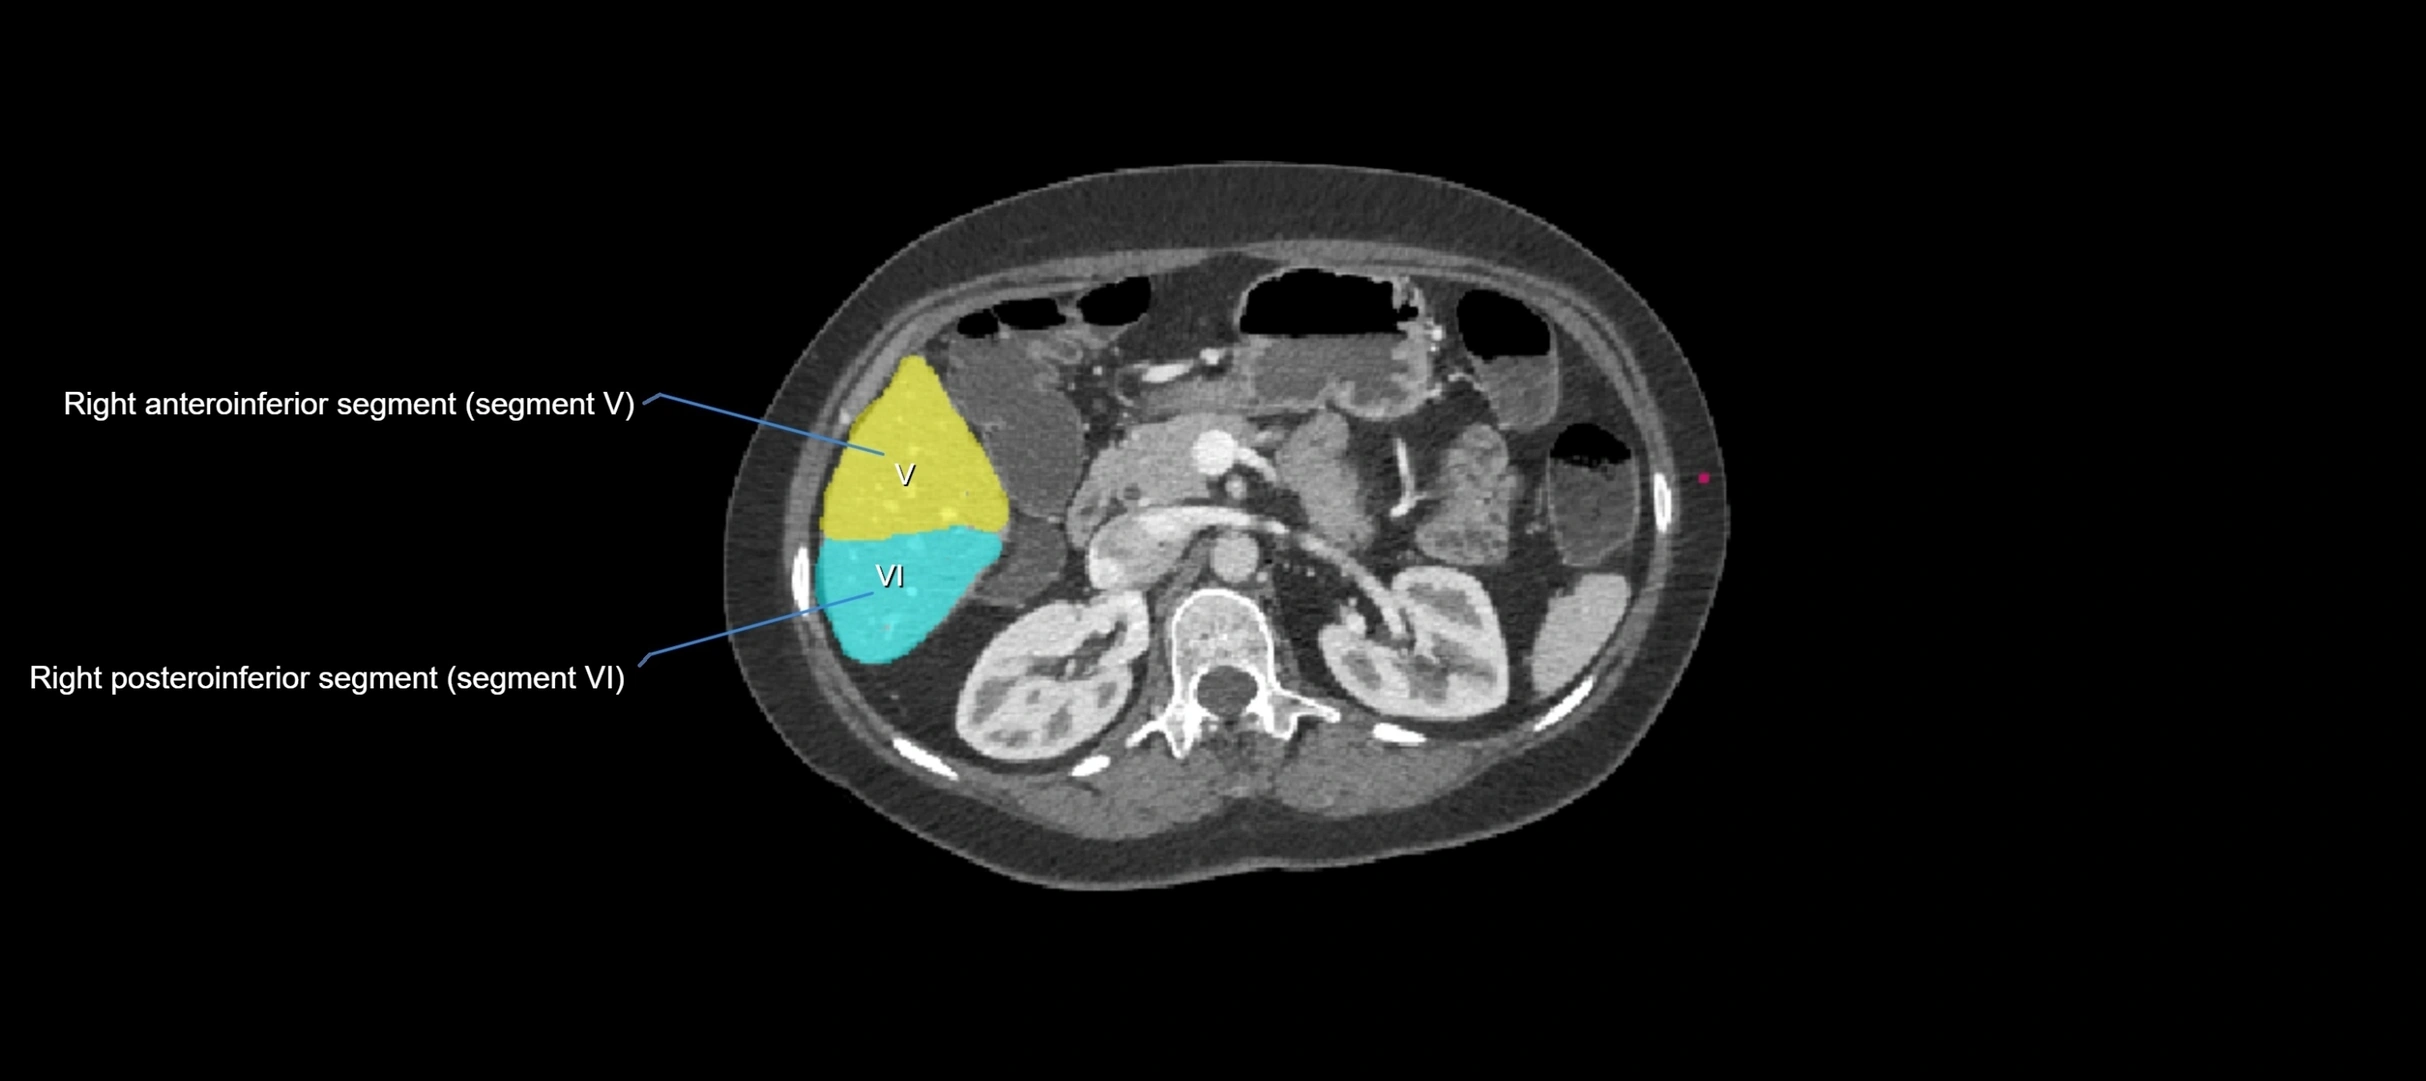

CT Image

image